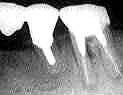

症例1

67歳・女性

術前3年

術直前(1985.9)

術直後

術後4年7ヵ月